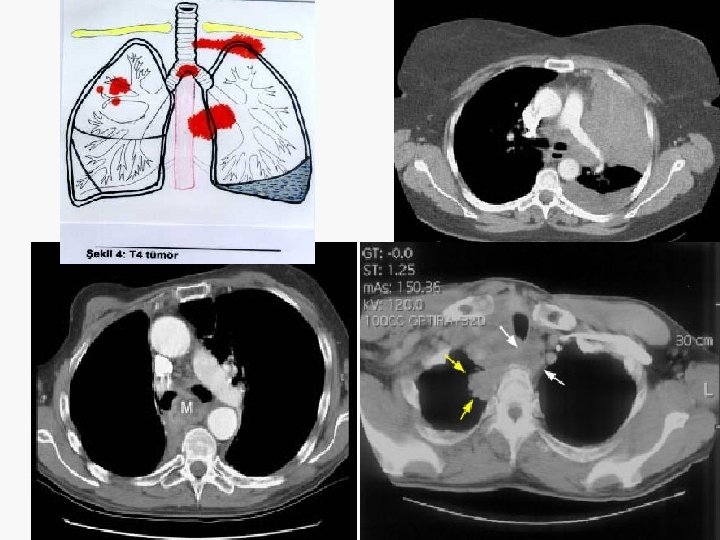

5. 4 cm

Evreleme EVRE 0 : Tis N 0 M 0 EVRE IA : T 1 N 0 M 0 EVRE IB : T 2 N 0 M 0 EVRE IIA : T 1 N 1 M 0 EVRE IIB : T 2 N 1 M 0 T 3 N 0 M 0 EVRE IIIA : T 1 -3 N 2 M 0 T 3 N 1 M 0 EVRE IIIB : T 4 N M 0 T N 3 M 0 EVRE IV : T N M 1